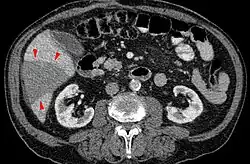

Der Verschluss einer (funktionellen) Endarterie führt zum anämischen Infarkt. (Beispiel: Niereninfarkt)

Häufigste Ursache eines anämischen Infarktes ist die Verschleppung eines Thrombus (Embolie) in ein arterielles Gefäß. Da es beim anämischen Infarkt keine oder kaum Kollateralgefäße gibt, führt die resultierende Blutleere (Ischämie) zu dem Erscheinungsbild eines sog. „weißen Infarktes“.

- Niere: als Niereninfarkt meist nach embolischem Verschluss einer kleinen Nierenarterie, seltener als hämorrhagische Infarzierung